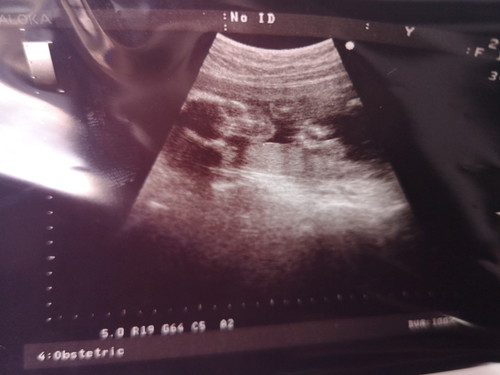

แม่ๆช่วยดูผลอันตร้าซาวด์หน่อยค่ะ

หมออันตร้าซาวด์ตอน4เดือน เกือบจะ5เดือน หมอบอกว่าน่าจะเป็นผู้ชาย แต่หลายคนทักว่าลักษณะเหมือนได้ลูกผู้หญิงแม่เลยไม่แน่ใจและอยากรู้มากว่าหญิงหรือชาย ดูจากฟิมล์แล้วก็ดูไม่ออกเลยค่ะ หมอนัดอีกทีเดือน ก.ค. รบกวนแม่ๆที่อ่านผลเป็นช่วยดูให้แม่หน่อยค่ะ

กำลังจะเป็นแม่